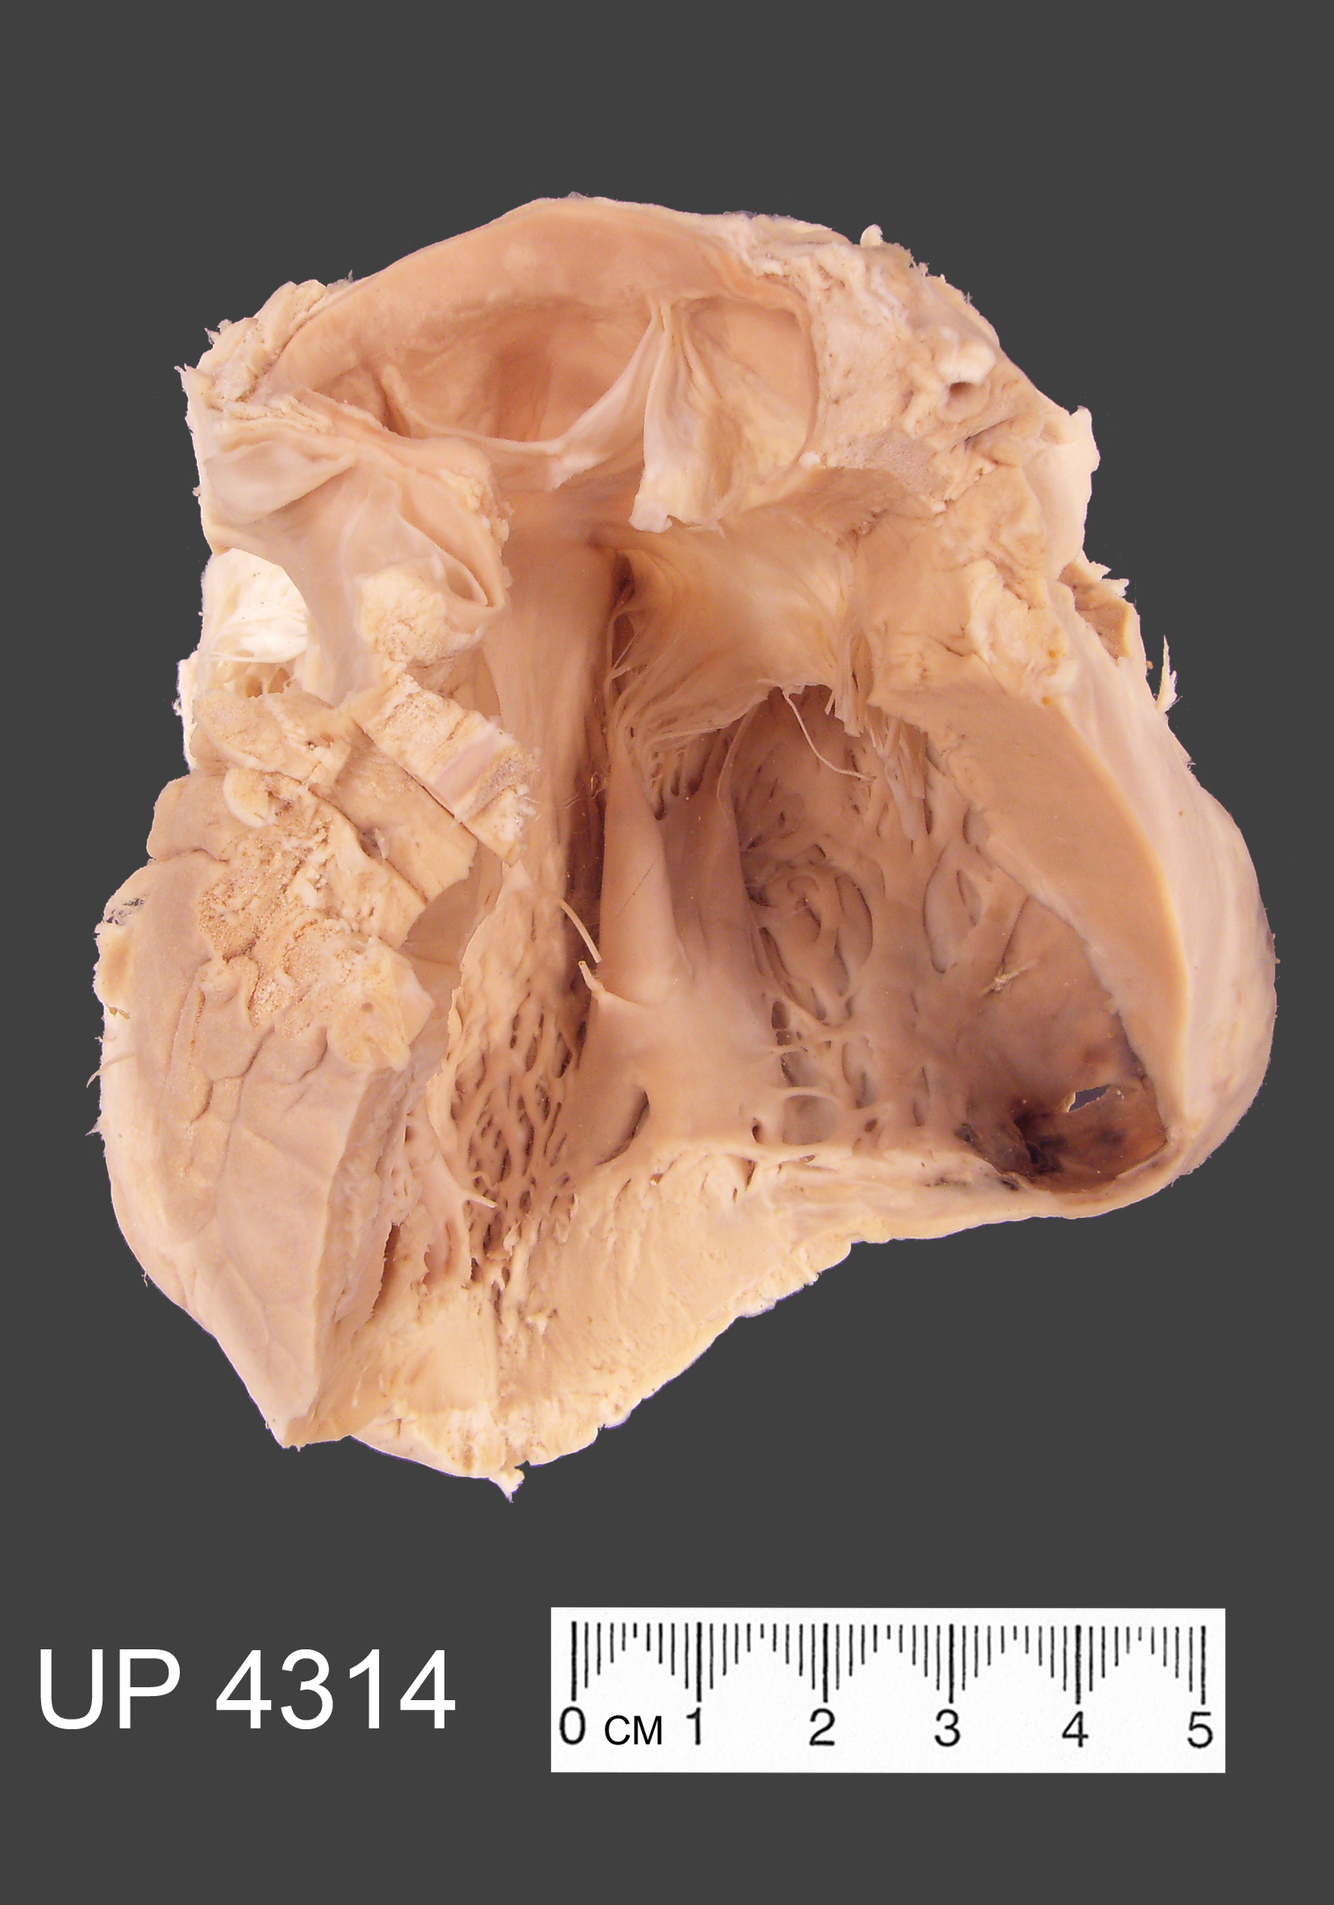

This mounted specimen shows a bisected heart.

The pericardium is partly covered by a shaggy fibrinous exudate with associated congestion and hyperaemia of the underlying tissues.

This appearance is described by pathologists as a “bread and butter” pericarditis because it looks like the butter of a bread and butter sandwich that has been pulled apart!

Other features include some minor atherosclerosis. seen in the large blood vessels.

Microscopically, the myocardium revealed scattered focal lymphocytic collections and the pericardium was coated by a fibrinous exudate.

The pathology is consistent with a viral myocarditis and pericarditis.